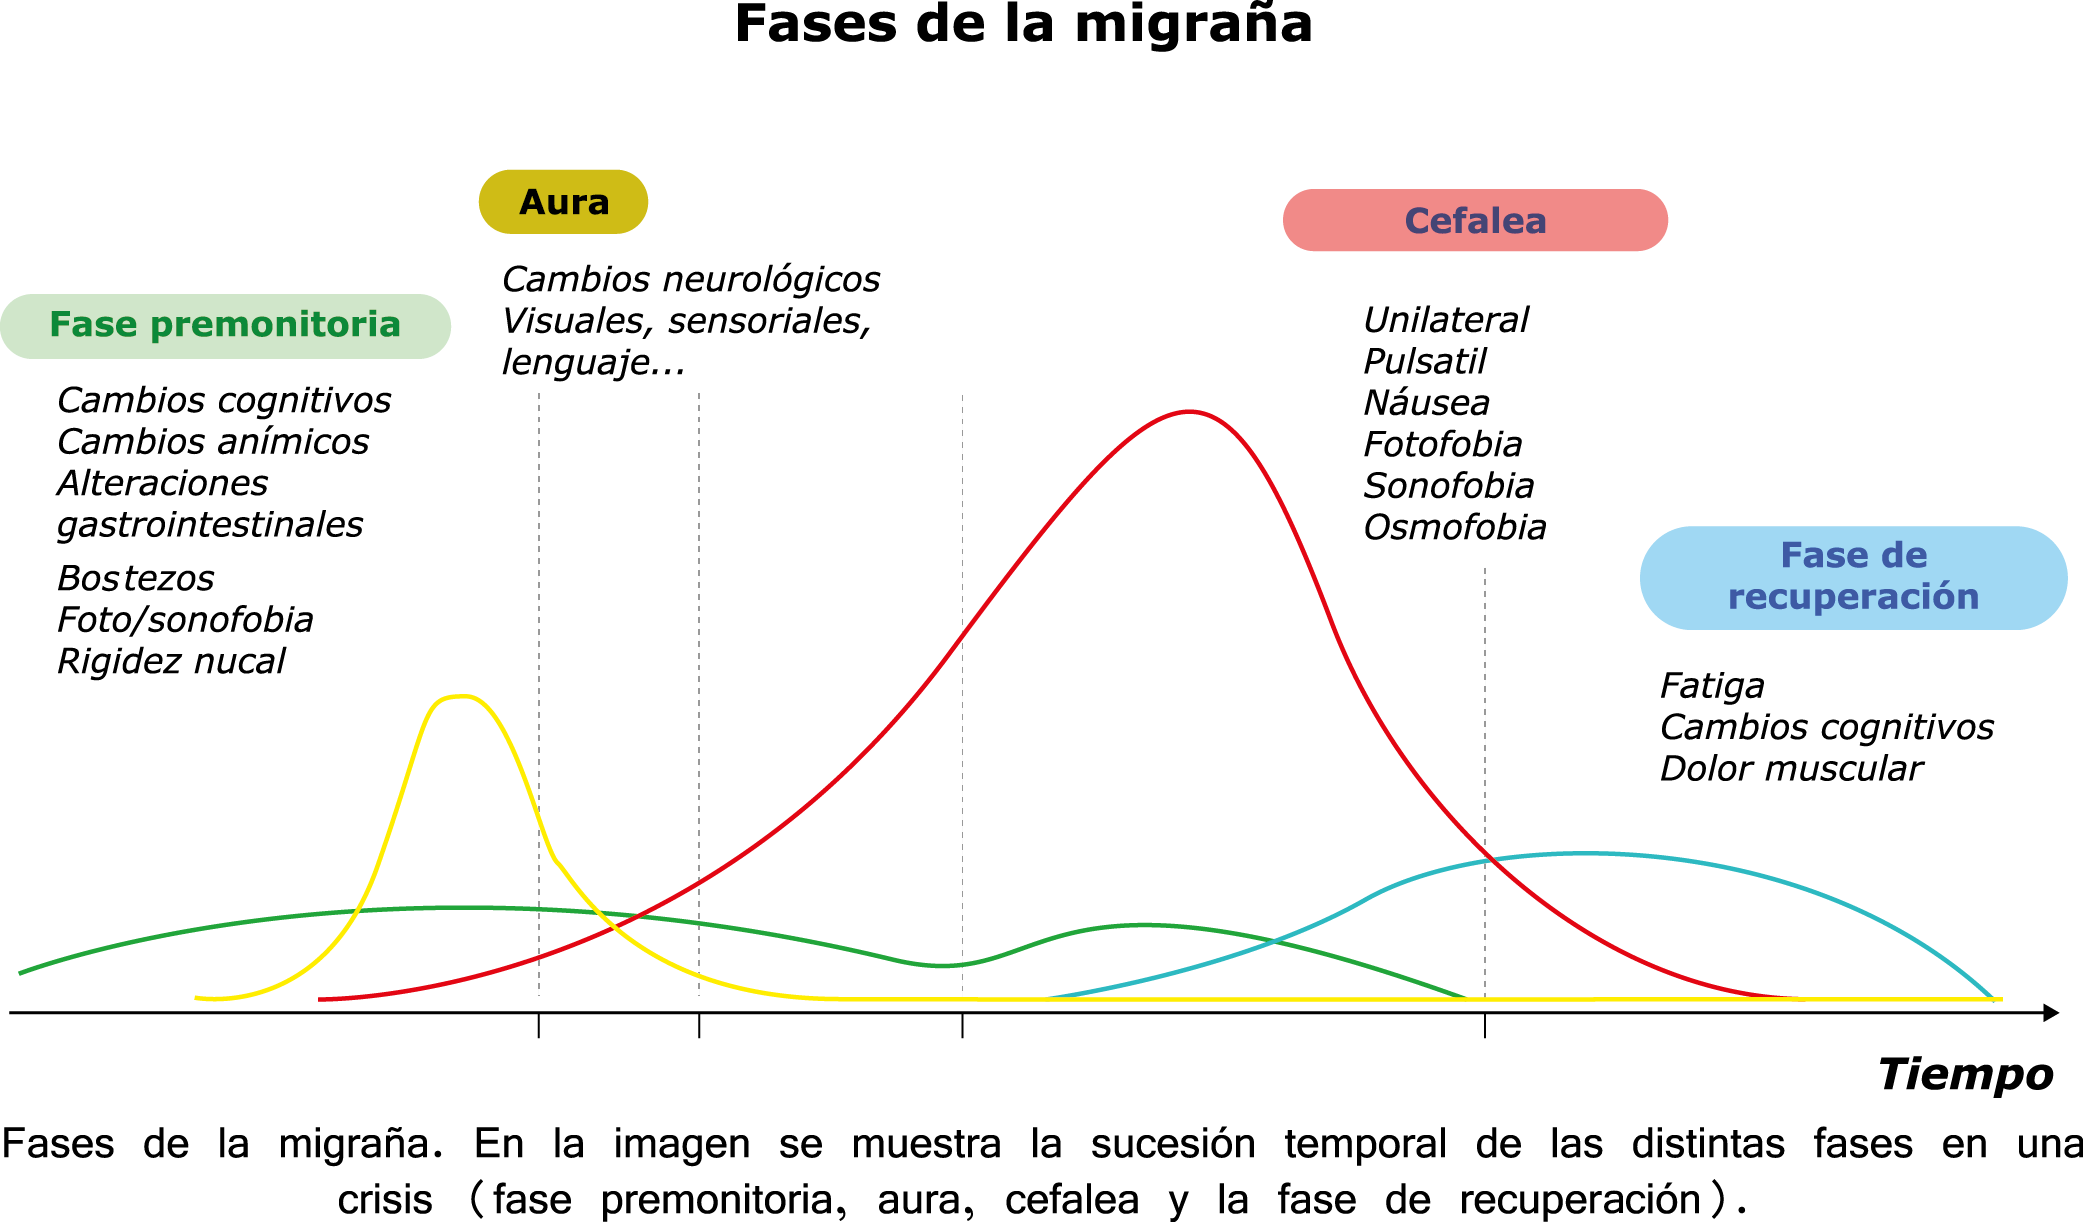

Todo lo mencionado contribuye al fenotipo del migrañoso y son vías que continuamente se están explorando para el desarrollo de nuevas terapias agudas y preventivas del dolor, más seguras y eficaces. Sin embargo, existe una controversia que gira en torno a dos cuestiones: la iniciación y el origen del dolor además de que todavía no se conoce el origen de los mecanismos neuronales que subyacen a la condición primaria en las personas susceptibles. Definitivamente la migraña implica la activación y sensibilización de las vías trigeminovasculares, así como el tronco cerebral y los núcleos diencefálicos(88). La vía aferente comienza en las aferentes vasculares nociceptivas de la duramadre que están para advertir, no para localizar. Su proyección al tálamo y la corteza y como se regula esta vía en cada nivel y por múltiples sistemas, ofrece la posibilidad de comprender los síntomas complejos y orientar las terapias. Los ataques comienzan como síntomas premonitorios, dificultad para concentrarse, bostezos, fluctuaciones del humor; y cambios homeostáticos, como la alimentación y el equilibrio de líquidos, que pueden incluir sensibilidades más generalizadas, como fotofobia y fonofobia. La fase premonitoria da paso a la fase de dolor con el sufrimiento acompañante y termina en una fase posdrómica de sentirse agotado por la experiencia. (Figura 1)

En la primera fase (figura 3), premonitoria, que precede a la cefalea, los sistemas del tronco encefálico y diencefálico modulan las señales aferentes, la fotofobia a la luz o la fonofobia al sonido, comienzan a disfuncionalizarse y eventualmente a evolucionar a la fase de dolor y con el tiempo a la fase de resolución o posdrómica. Aproximadamente en un tercio de los pacientes con migraña, sus ataques están asociados con déficits neurológicos, que incluyen perturbaciones corticales, denominadas colectivamente aura de migraña(3).

Siendo un trastorno cerebral complejo y multifacético que en su totalidad puede durar varios días, se ha dividido clásicamente en cuatro fases: premonitoria, aura, cefalea y postdrómica. Estos pueden ocurrir en un orden secuencial lineal, pero en la mayoría de los casos, las fases de la migraña muestran una significativa superposición, de modo que el orden lineal es a la vez atractivo y engañoso en su simplicidad. Es importante recalcar que algunos síntomas, como el cansancio o el deterioro de la concentración, bien pueden presentarse en todas las fases. En realidad, solo el dolor de cabeza, por su ausencia o presencia, es quien se destaca, aunque, como se verá, es solo parte del cortejo sintomático.